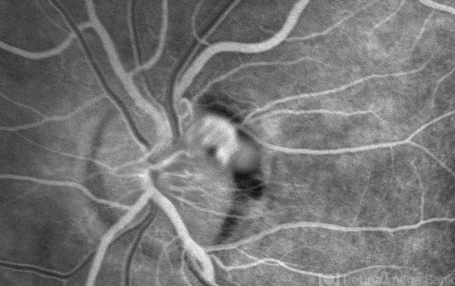

- Unusual presentation of VHL juxtapapillary hemangioblastoma detached from retina with feeder vessels

- Von Hippel-Lindau, retinal hemangioblastoma

- 30-year-old female with fhx VHL and CNS hemangioblastomas and visceral lesions. P/C with a floater (no PVD or VH) after episodes of vomiting.